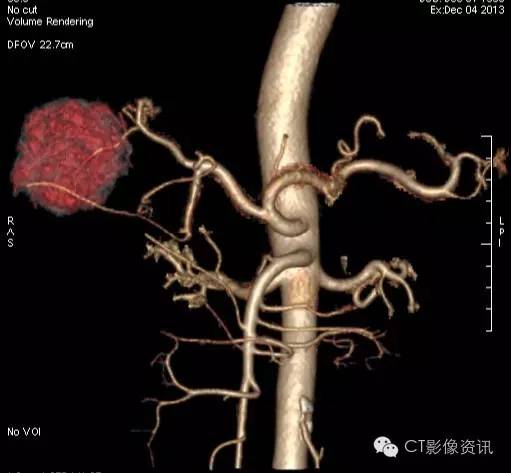

VR图像清晰显示病灶的供血动脉

此外,使用单能量低keV图像观察,更有利于肝癌供血小血管的显示。